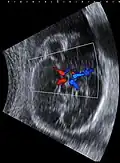

Fetal ultrasound image at the level of circle of Willis, showing PCA, MCA and ACA -